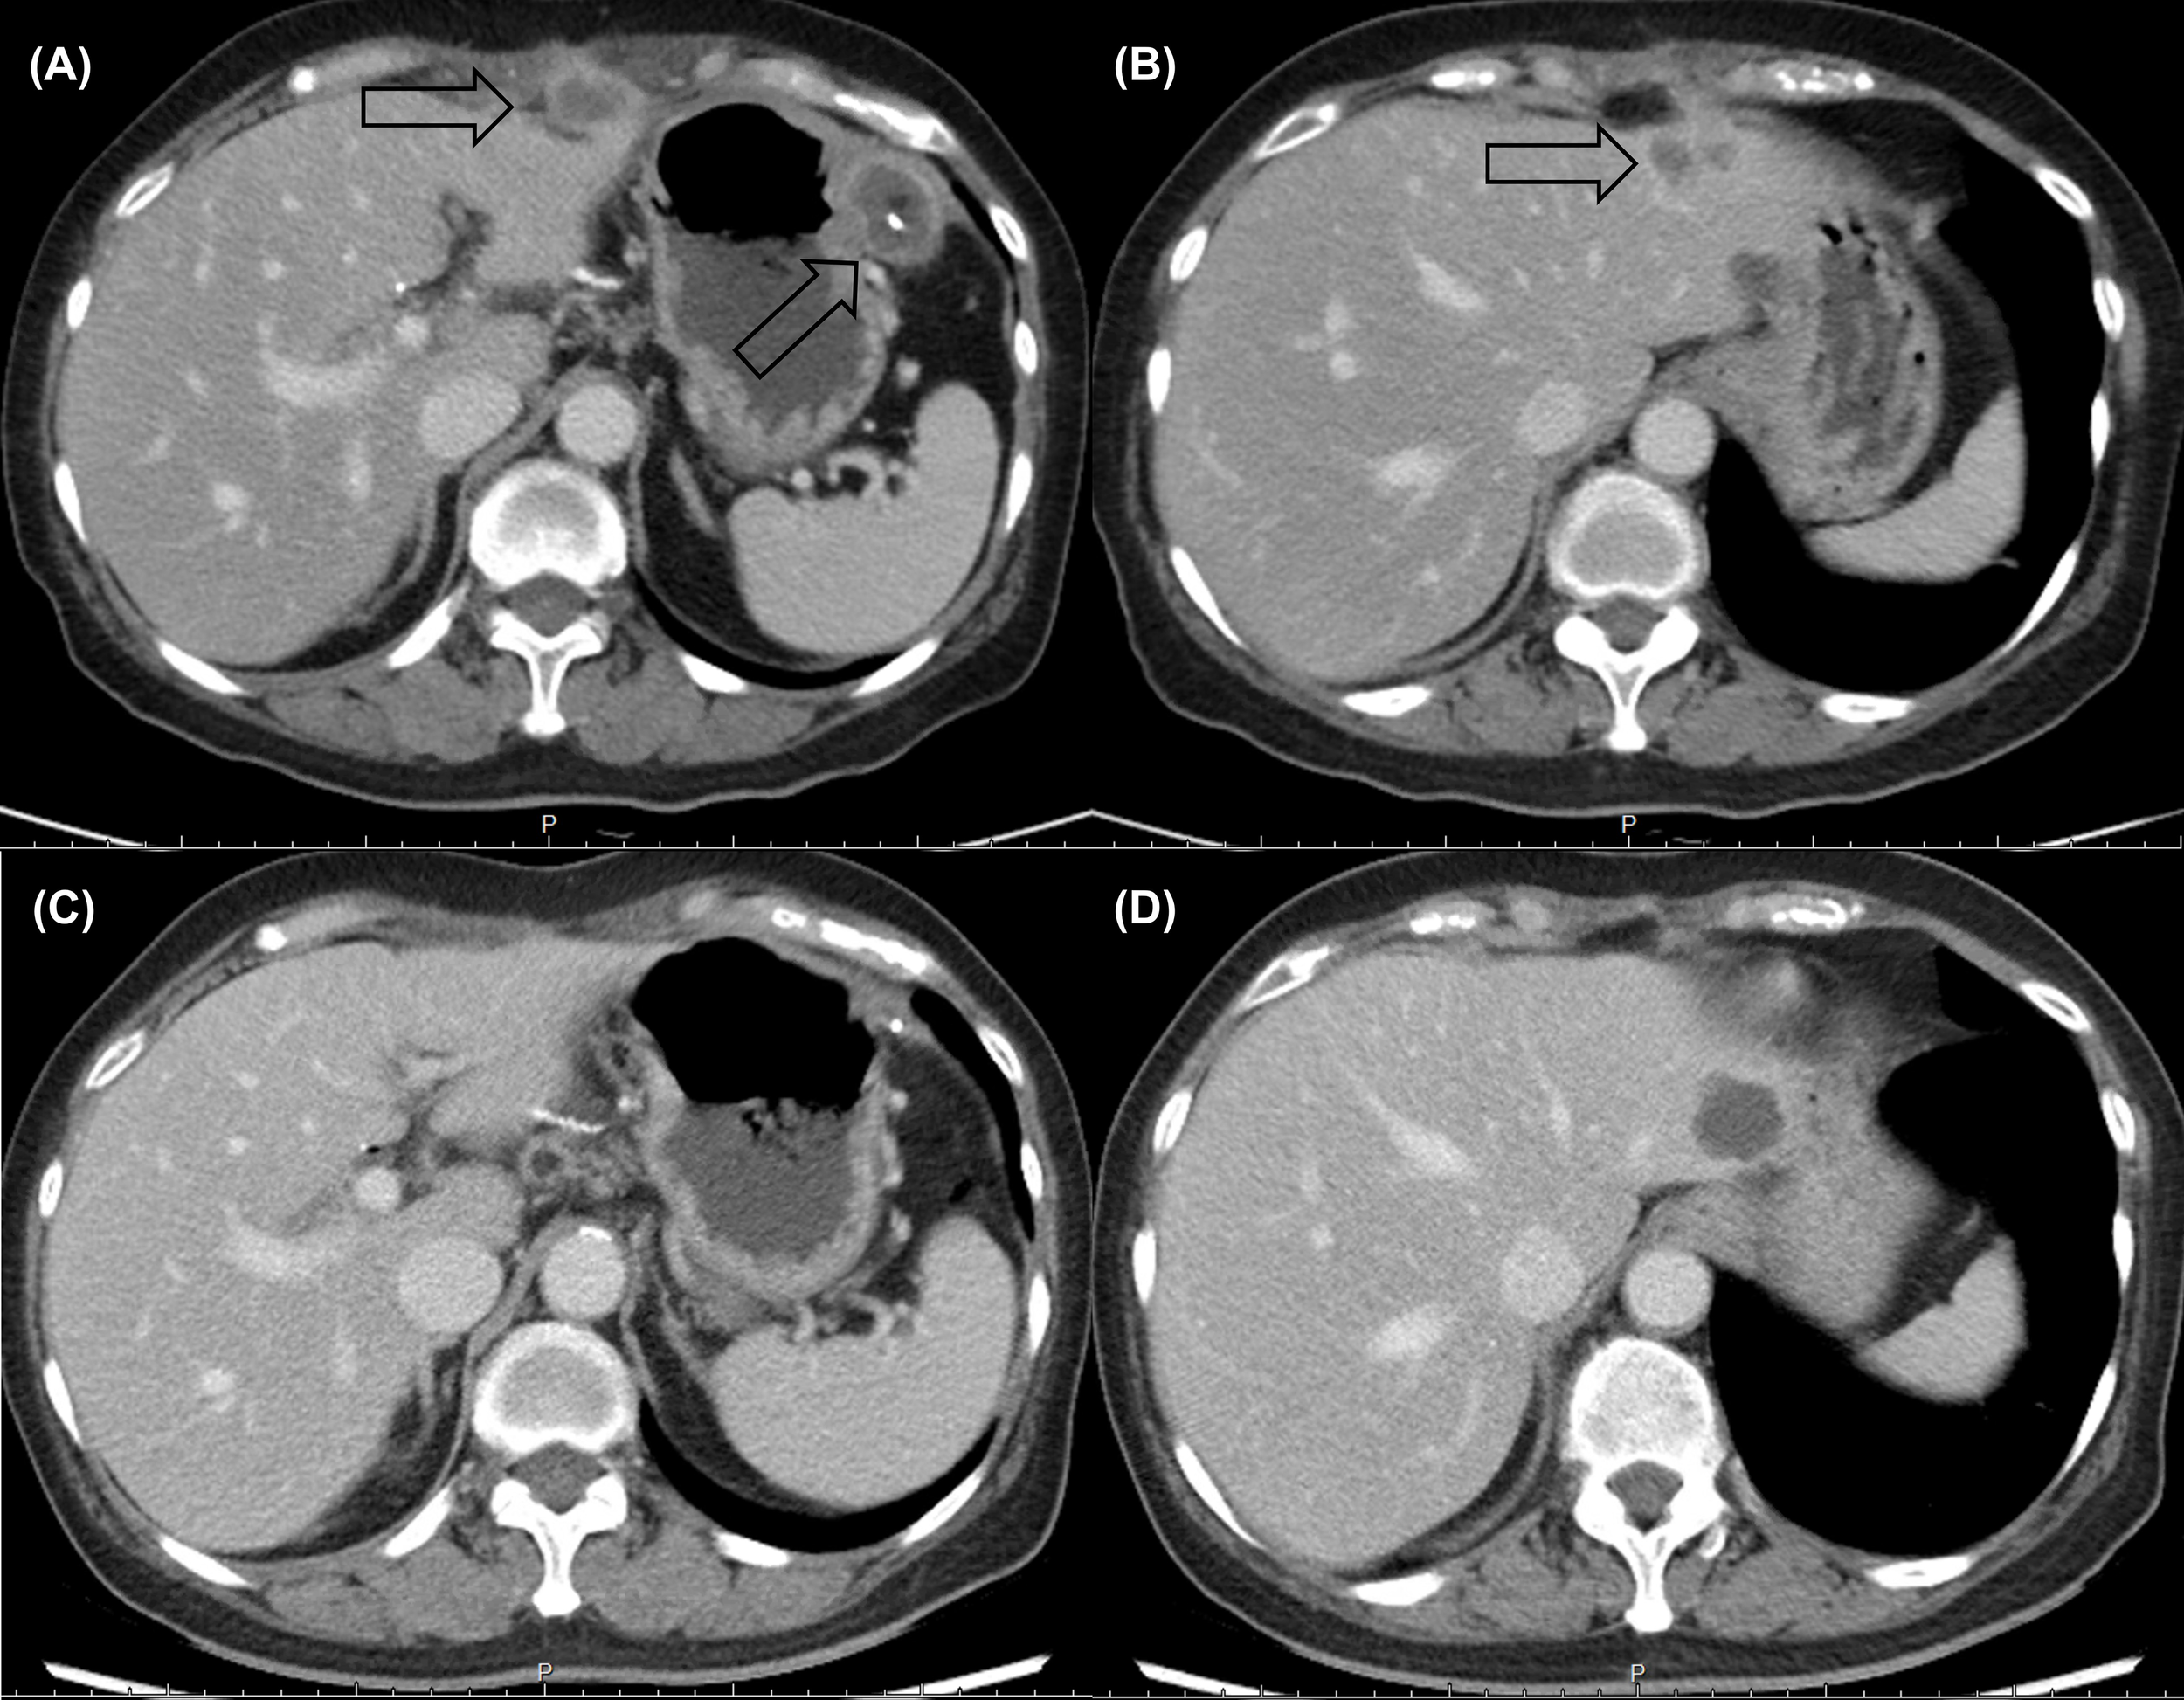

Following eight cycles of NaFL, peritoneal metastases progressed with new liver metastases (Figures 1A, B). Based on the results of genetic tests, standard-dose anti-programmed cell death 1 (anti-PD-1) therapy was recommended, but this treatment was not affordable for the patient. With the approval of the patient, a biweekly low dose of nivolumab (0.3 mg/kg, 20 mg) combined with cisplatin (40 mg/m2), gemcitabine (500 mg/m2), S-1 (20 mg bid), and leucovorin (15 mg bid) was started in February 2021. After six cycles of nivolumab with chemotherapy, in April 2021, computed tomography revealed marked tumor reduction. Because of cisplatin-associated renal dysfunction and extreme tumor reduction, nivolumab, S-1, and leucovorin have been administered without gemcitabine and cisplatin since July 2021. With ongoing low-dose nivolumab plus S-1 and leucovorin for more than 1 year, CR has been maintained (Figures 1C, D), and she has remained asymptomatic with gradually recovered renal function. The treatment course is summarized in Figure 2.

Figure 1

Computed tomography revealed multiple rim-enhancing (A) peritoneal metastases and (B) liver metastases before low-dose nivolumab. A durable complete response (C, D) was maintained after more than 1 year of nivolumab-based treatment.